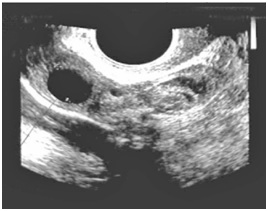

При поступлении пациентка К. была направлена к врачу ультразвуковой диагностики для проведения ультразвукового исследования органов малого таза. УЗИ проводилось на ультразвуковом сканнере «Phillips HDI 1500» вагинальным датчиком датчиком в режиме 2D c применением цветного допплеровского картирования. По данным проведенного исследования: тело матки размером 45х40х45 не увеличено, толщина эндометрия 13,5 мм, строение эндометрия не изменено. Левый яичник б/о, правый яичник увеличен в размере 50х42х48мм,в нем визуализируется желтое тело диаметром 17мм , рядом с желтым телом визуализируется округлое образование 27х24мм без четких контуров, гетерогенной структуры, в центре образования визуализируется анэхогенное включение диаметром 10мм, напоминающее плодное яйцо.

При ЦДК картировался интенсивный кровоток по периферии образования. Контур правого яичника нечеткий, неровный. В заднем своде жидкость в небольшом количестве.

Заключение: Эхо- признаки внематочной яичниковой беременности .Данные гормонального исследования показывали повышение уровня хорионического гонадотропина до 1742,3 МЕ/л. Женщина К. была прооперирована по поводу внематочной беременности. Гистологические исследования, проведенные в дальнейшем, подтвердили факт яичниковой беременности. При дальнейшем контроле уровня ХГЧ отмечено его снижение до 287.4 МЕ/л.